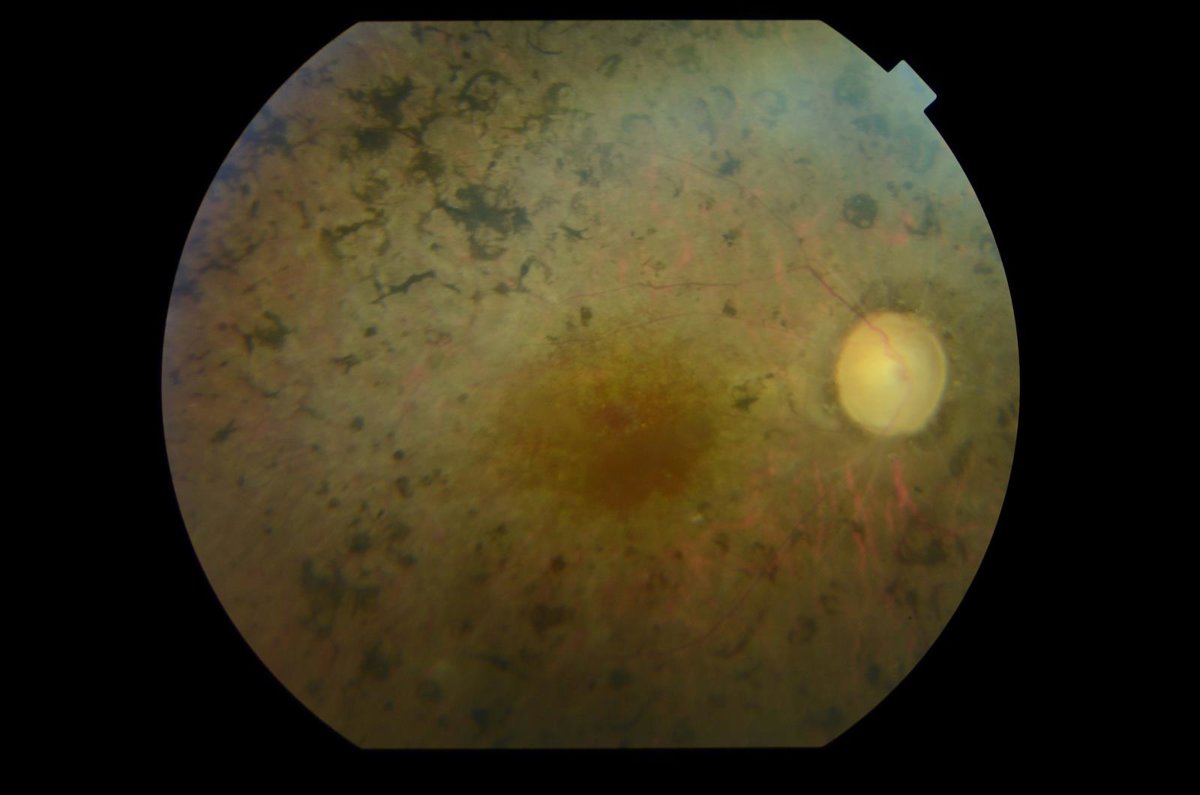

Retinosis pigmentaria

SparingVision es una compañía especializada en el desarrollo de terapias innovadoras para el tratamiento de enfermedades oculares hereditarias y, en particular, el tratamiento de la retinosis pigmentaria, que es causante de ceguera de dos millones de pacientes en el mundo.

En esta ampliación de capital permitirá a la compañía avanzar en el desarrollo de SPVN06, su terapia para el tratamiento de la retinosis pigmentaria. En particular, financiará las actividades de fabricación y regulatorias requeridas para poder empezar su primer ensayo clínico en humanos, previsto para 2021, y ampliar el equipo para iniciar las operaciones en EE.UU.